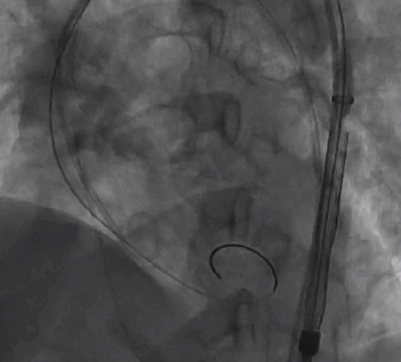

手术过程概览:

主动脉根部造影提示瓦氏窦整体形态偏小,决定给予冠脉保护

导丝左冠保护

导丝跨瓣

18mm球囊预扩,无明显腰征,少许瓣周漏,未见冠脉阻挡,决定选择TaurusOne®AV23瓣膜。

TaurusOne®轻松过弓

TaurusOne®释放过程:

瓣膜定位

瓣膜释放后形态位置良好,造影无返流